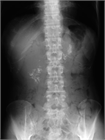

1. 膵管内の結石(膵石)を認めた場合と、膵全体に分布する複数かつびまん性の石灰化を認めた場合は慢性膵炎と診断できる(推奨度1)

1. 加齢現象に伴い膵石が観察される場合がある。

1. 石灰化を伴った膵腫瘍がまれに存在する。